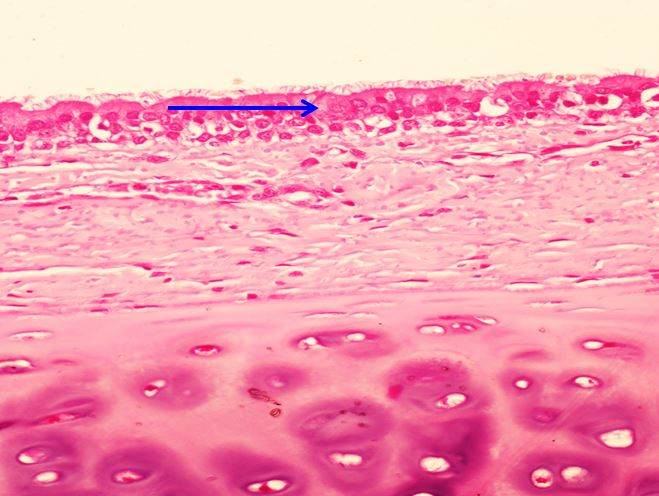

_Giác mạc:

Biểu mô lát tầng không sừng hoá

Màng Bowman

Nhu mô (lớp đệm)

Màng Descemet

Nội mô giác mạc: biểu mô lát đơn